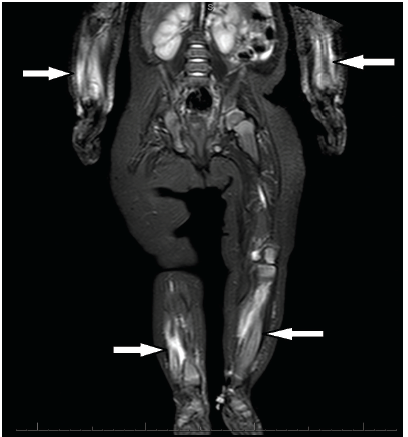

Benjamin C. Lee, MD

A healthy, 5-month-old girl presented with a 3-day history of bilateral leg pain and associated crying, particularly when her parents held her legs during diaper changes.